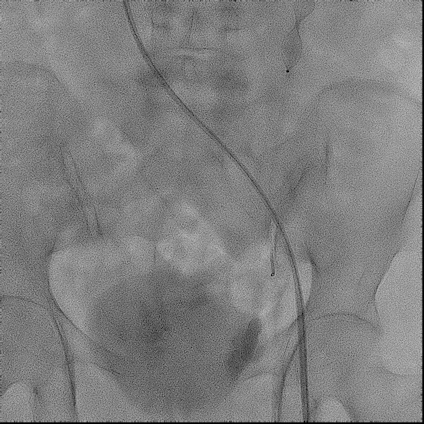

手术过程(三):

交换置入8 F-55 cm长鞘至卵巢静脉近端,经鞘内推送AVP Ⅱ,由于35导丝的强支撑性可以使AVP Ⅱ定位更加精准,选择于近段卵巢静脉释放,鞘内造影见AVP Ⅱ完全释放,VR导管经Stiff导丝置于卵巢静脉远端。